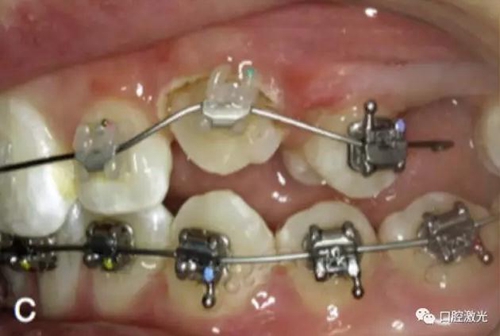

相比之下,激光開窗導(dǎo)萌有很多優(yōu)點,如果有足夠的角化組織,那么是可以采用激光進行開窗手術(shù)實施導(dǎo)萌,并立即粘接托槽。因此,同樣可以節(jié)省患者的等待時間。另外,口腔激光的止血特性可以提供清晰的視野,也有助于術(shù)后立即粘接托槽。

治療前

激光牙齦切割后即刻

粘接托槽

3周后效果